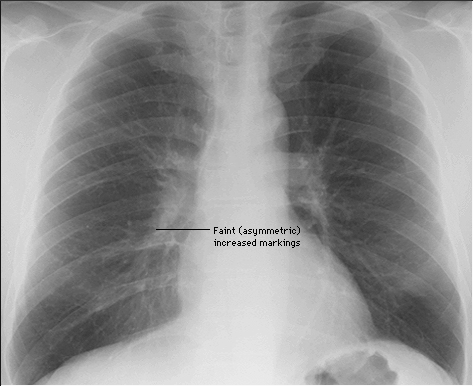

Рентгеновские снимки и анализы при правосторонней пневмонии